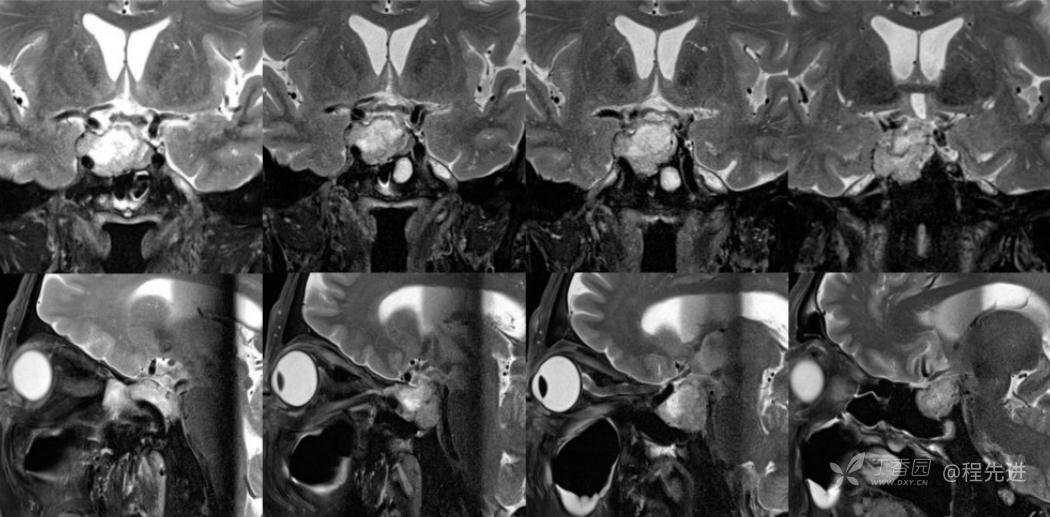

MR:

T2